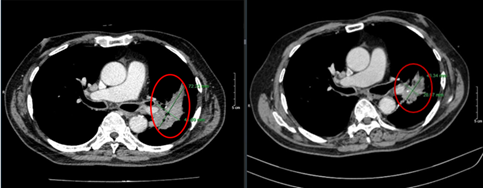

Hình 1: U trung tâm phổi trái (vòng tròn đỏ) kích thước 72*41mm trên của sổ nhu mô và cửa sổ trung thất

Hình 7.1: Cắt lớp vi tính ngực ở cửa sổ nhu mô

Hình 7.2: Hình ảnh cắt lớp vi tính ngực ở cửa sổ trung thất

Kết luận: Hình ảnh chụp cắt lớp vi tính ngực: sau 6 đợt điều trị khối u (vòng tròn đỏ) giảm kích thước từ 72x41mm (bên trái) xuống còn 43x28mm (bên phải)

Hình 8: Hình ảnh CT ngực: Sau 6 đợt điều trị hạch trung thất giảm kích thước từ 11x18mm trước điều trị (mũi tên vàng) xuống còn 8x10mm sau điều trị (mũi tên đỏ)